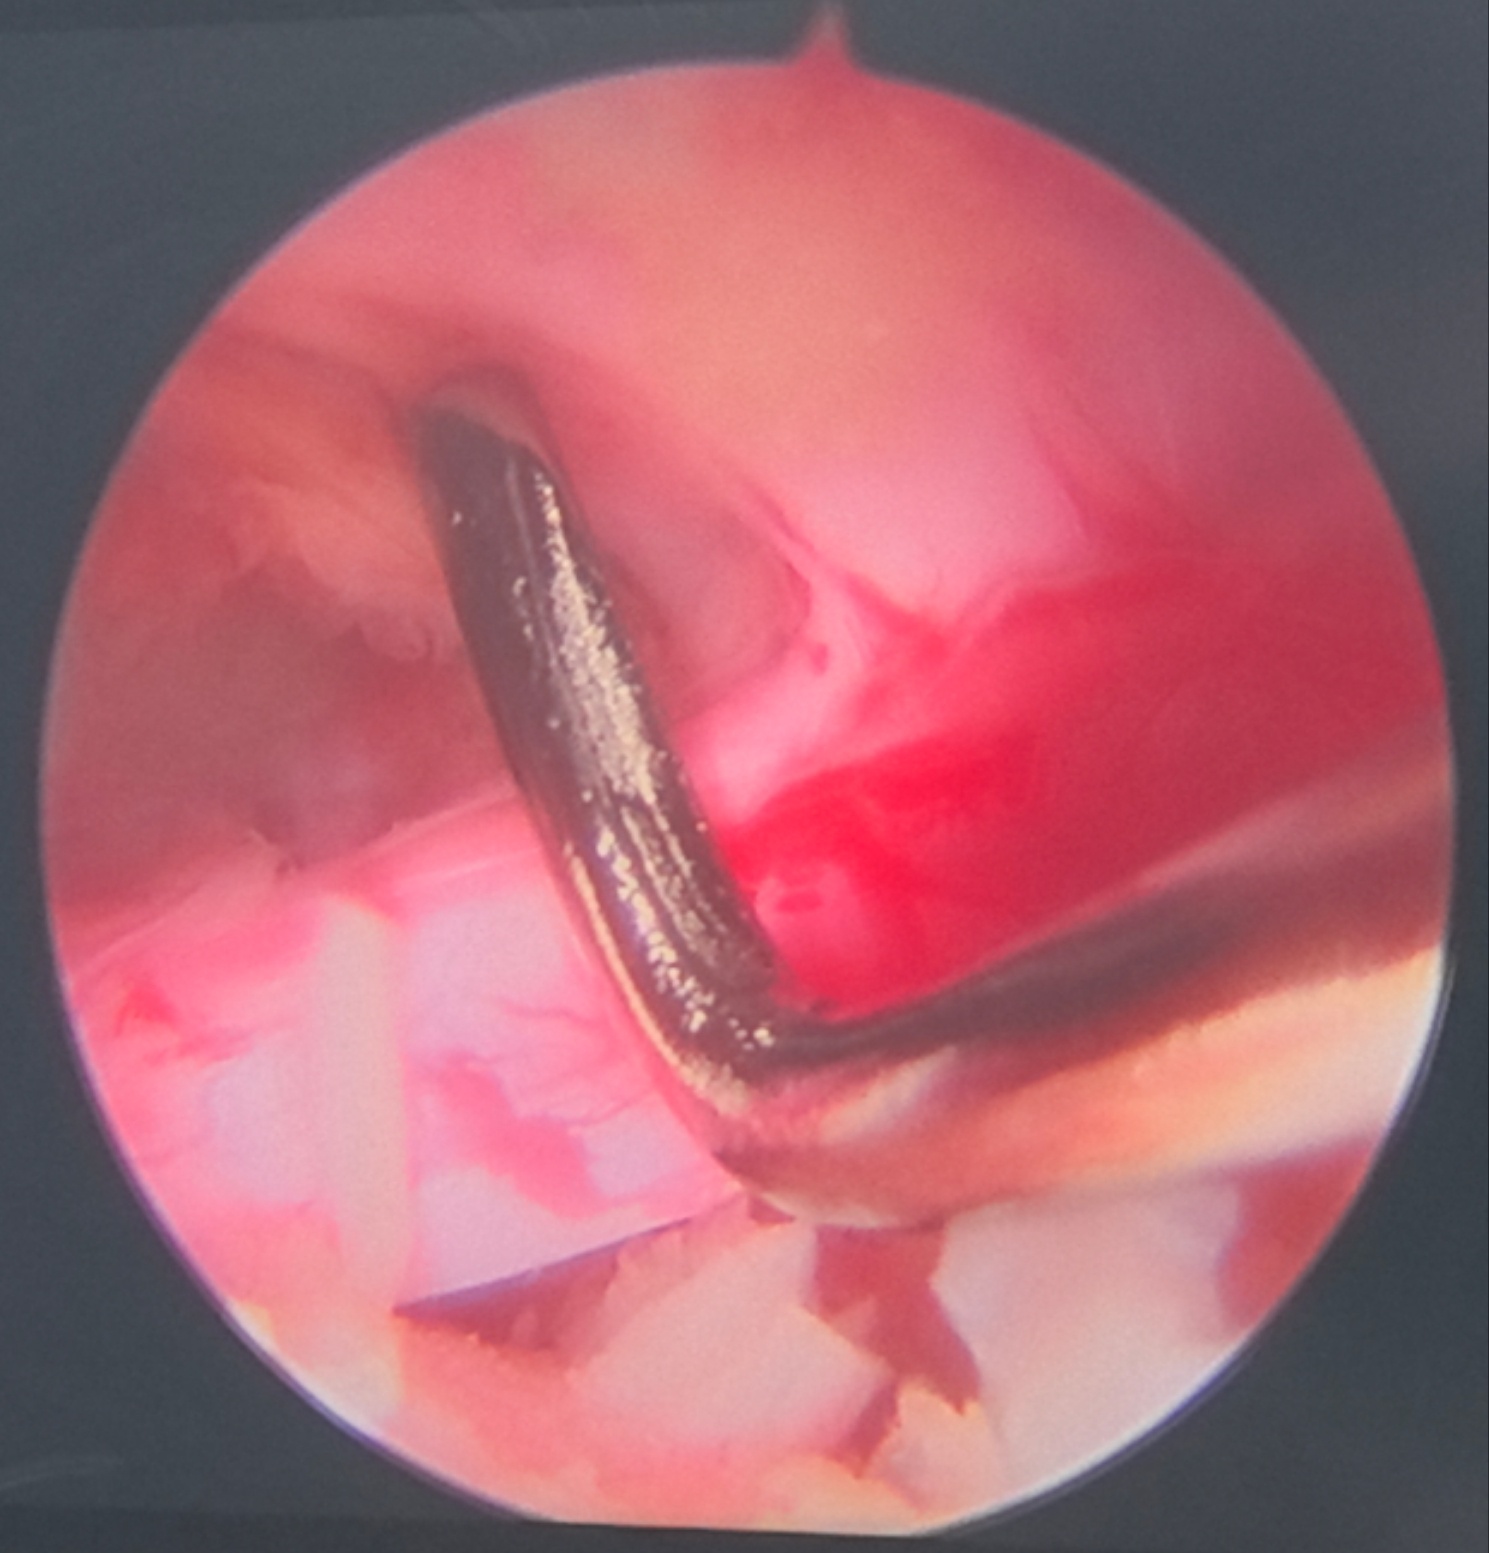

2024年我来到同济光谷院区脊柱微创中心工作,这一年里,我的绝大多数腰椎手术,大部分颈椎手术和小部分胸椎手术都是微创。脊柱微创手术占比,全科室最高。尤其是颈椎微创,应该是这个大区域里做的最多的医生了。做的越多,感觉微创优势越大,内镜是深入手术野的显微镜,创伤小,看的更清楚,病人康复快。 更重要的是,微创让不可能成为可能,化腐朽为神奇。这个患者腰椎感染,腰腿疼痛剧烈,卧床不起两月,有心脏病,肝硬化,腹水,巨脾,消化道溃疡,手术风险极大。患者强烈要求手术,而且抱着不成功便成仁的决心:如果术中术后有生命危险,他拒绝进ICU抢救。这种手术谁敢做? 我做了微创手术,他术后三天就可以坐起来,走路了,看他的微笑。 2025-01-15 18:23